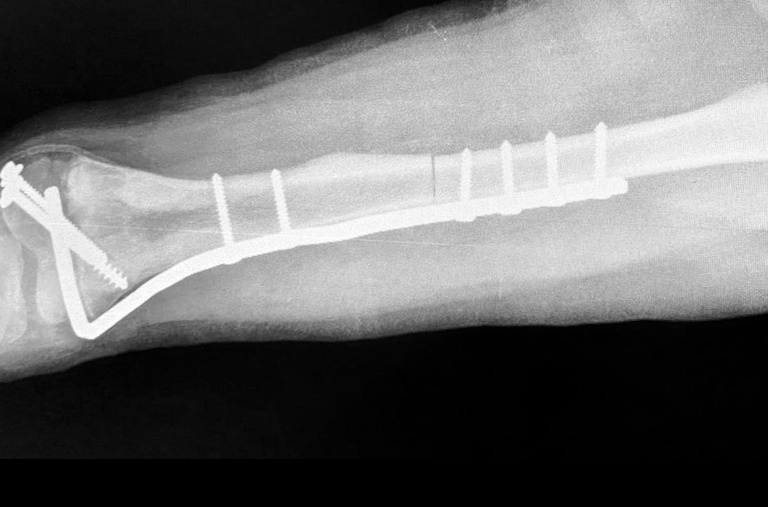

Uma extensão de 14 cm de fêmur foi extraída, submersa em nitrogênio a 196ºC negativos e reinserido no paciente

O procedimento realizado na última segunda-feira, 10, teve seis horas de duração e foi realizado em um menino de nove anos de idade, natural de Araxá-MG, diagnosticado há três meses com um tumor ósseo raro. Uma extensão de 14 cm de fêmur foi extraída. A equipe médica removeu, desse segmento ósseo, a área acometida pelo tumor. O osso recebeu, então, um tratamento de submersão em cinco litros de nitrogênio, a 196ºC negativos, durante 20 minutos. Após 15 minutos em temperatura ambiente e outros 15 submerso em água destilada, o osso foi reinserido no paciente e fixado.